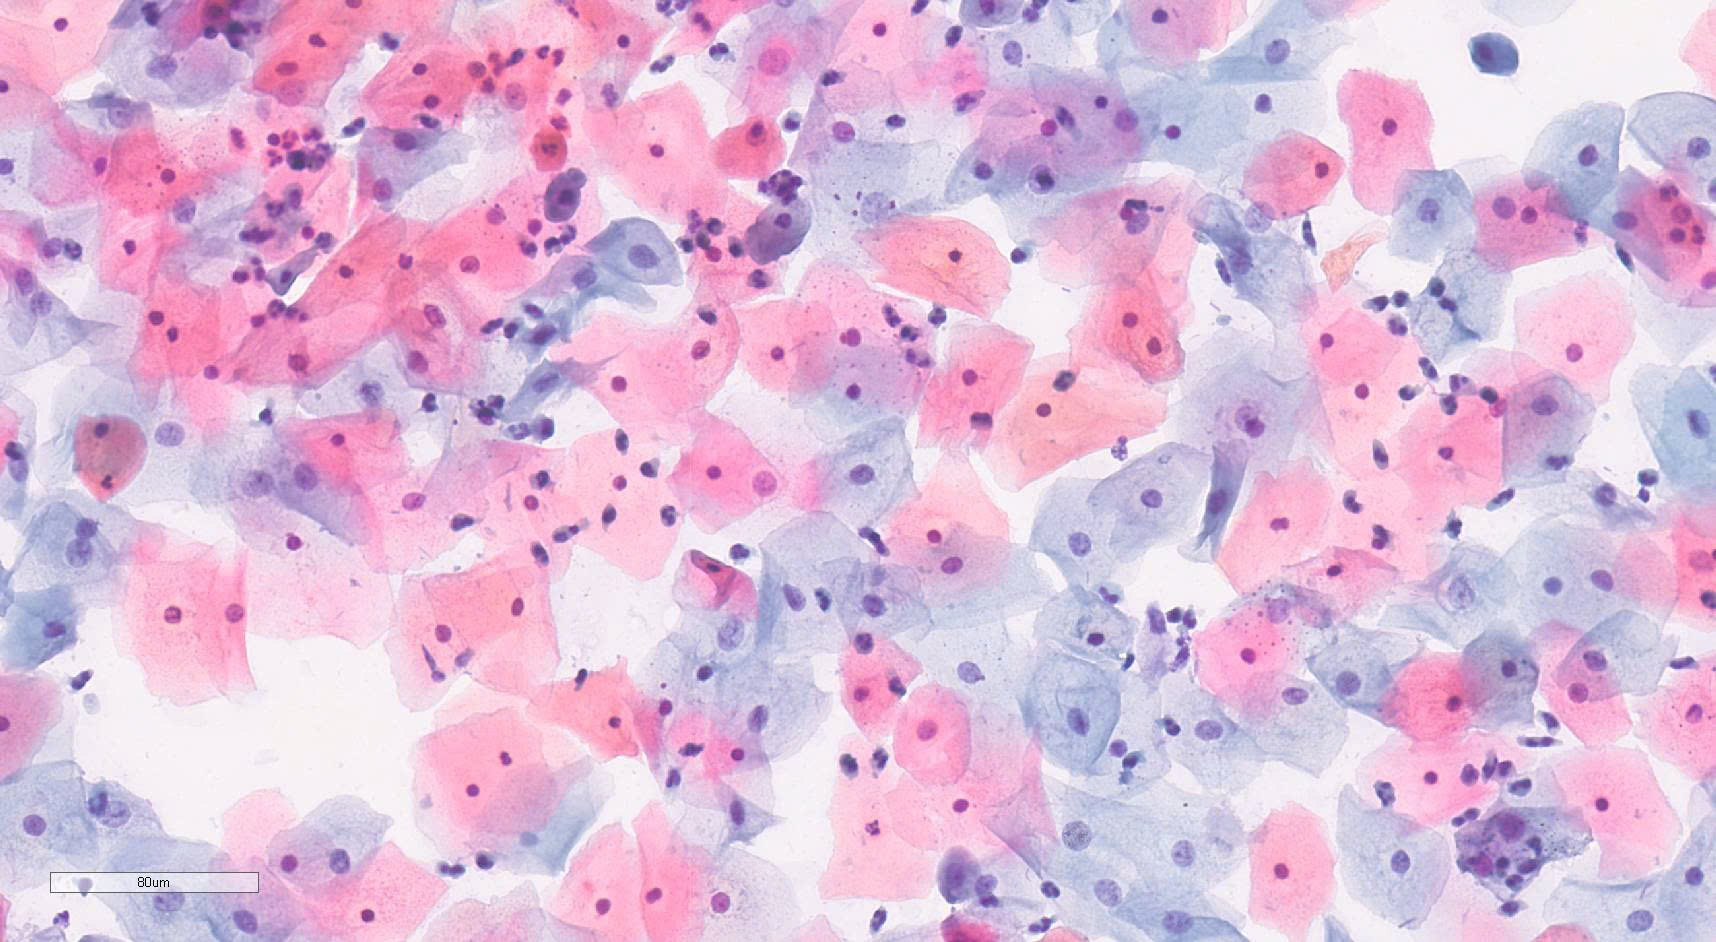

Xét nghiệm tế bào

Xét nghiệm phiến đồ Pap kinh điển và Pap mỏng

Chuyên đề tế bào học